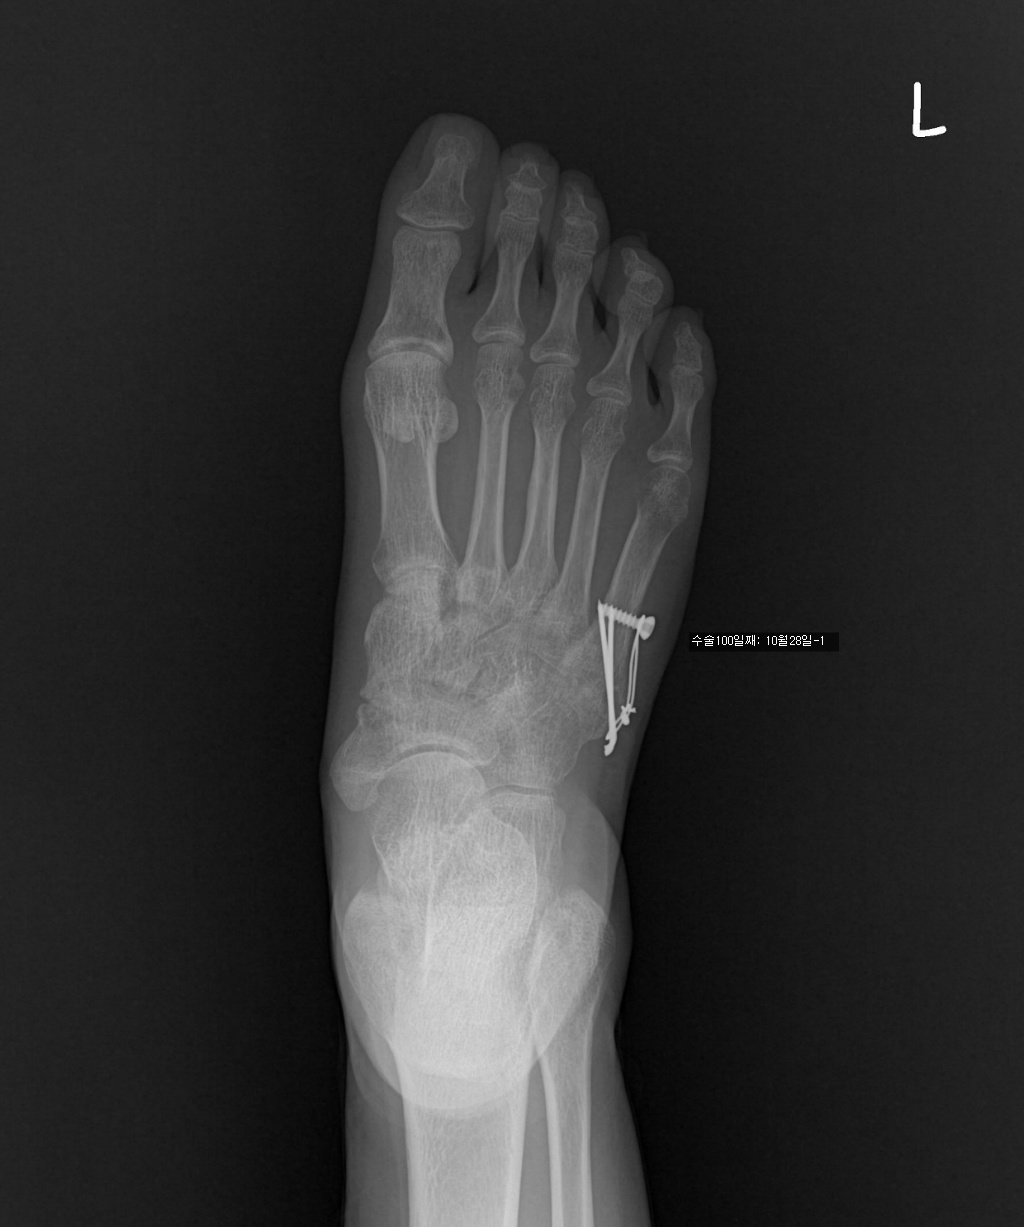

수술한지 100일 정도 됩니다.

7/17 : 출근 중 지하철 계단에서 구르는 사고로 좌측제5중족골기저부 골절

7/18 : 관헐적 정복 및 금속내고정술  시행 및 반깁스 (2주)

아래는 그간의 사진입니다. 제 눈은로는 수술직후의 사진과 3개월후의 사진의 차이를 잘 모르겠네요..